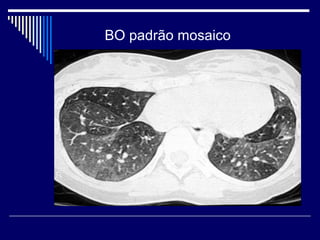

BO padrão mosaico